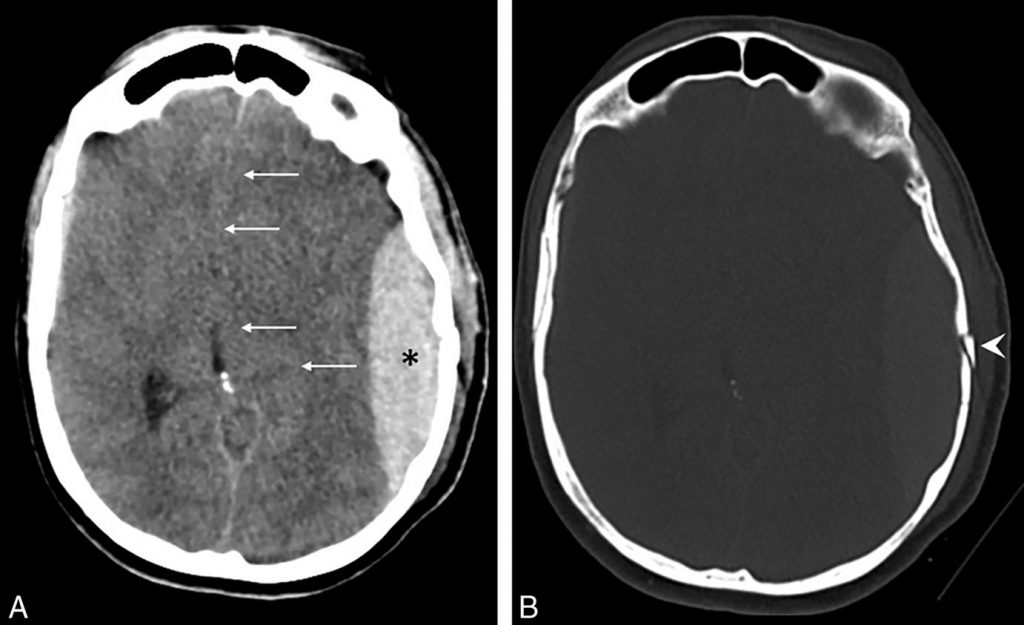

C’est une collection hyperdense au scanner, en forme de lentille biconvexe sous la table osseuse interne (figure 58.1), dont l’extension est limitée par les sutures mais pas par les sinus duraux, et qui est souvent associée à une fracture crânienne en regard. Elle est fréquemment de topographie temporopariétale.

L’effet de masse produit est variable, apprécié par le déplacement des ventricules et de la ligne médiane. Les signes d’engagement temporal ou sous-falcoriel (cf. chapitre 55) en représentent la gravité.

Fig. 58.1. Scanner cérébral. Hématome extradural temporopariétal gauche.

Scanner sans injection en coupe axiale en fenêtre parenchymateuse (A) et osseuse (B) : hyperdensité spontanée sous la table osseuse, en forme de lentille biconvexe (*), refoulant le parenchyme cérébral et responsable d’un effet de masse avec effacement et déplacement du ventricule latéral gauche (flèches). Fracture crânienne associée (tête de flèche).

Source : CERF, CNEBMN, 2022.